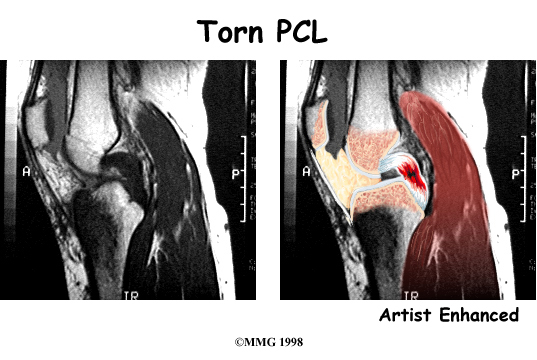

The magnetic resonance imaging (MRI) scan is probably the most accurate test without actually looking into the knee. The MRI machine uses magnetic waves rather than X-rays to show the soft tissues of the body. This machine creates pictures that look like slices of the knee. The pictures show the anatomy, and any injuries, very clearly. This test does not require any needles or special dye and is painless.

Ruptured PCL